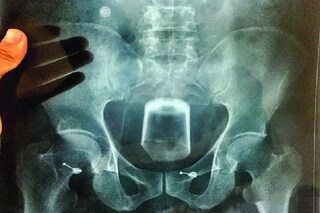

প্রথমে দেখা করার জন্য ডেকে পাঠিয়ে পরে যৌন সম্পর্ক স্থাপনের প্রস্তাব ৷ তাতে রাজি না হওয়াতে পাশবিক অত্যাচারের শিকার হতে হল যুবককে ৷ অভিযোগ, ব্যান্ডেল স্টেশনের কাছে একটি গলিতে সঞ্জয়কে টেনে নিয়ে যায় ফেসবুকের বন্ধু রিক ৷ তারপর তাকে রাগে মারধর করে রিক৷এতেই শেষ নয়, চুল কেটে, উপড়ে নেওয়া হয় ভুরু৷ রাগে সঞ্জয়ের মলদ্বারে কাঠের টুকরো ঢুকিয়ে দেয় রিক ৷

কোনওক্রমে ঘটনাস্থল থেকে পালিয়ে রক্তাক্ত অবস্থায় নির্যাতিত সঞ্জয় হাসপাতালে গিয়ে পৌঁছায় ৷ সেখান থেকেই খবর পান পরিবারের সদস্যরা ৷ পরে চুঁচুড়া থানায় অভিযোগ দায়ের করে সঞ্জয়ের পরিবার ৷